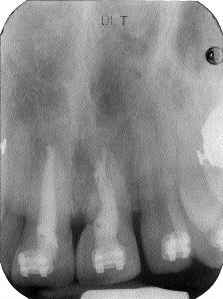

Final endo x-ray.